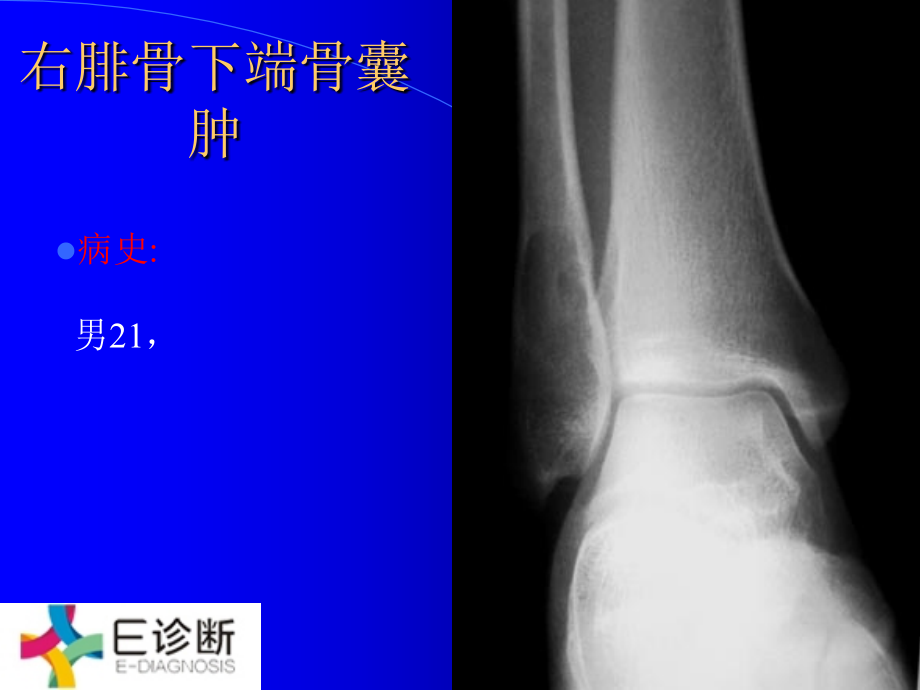

,单击此处编辑母版标题样式,*,单击此处编辑母版文本样式,第二级,第三级,第四级,第五级,右腓骨下端骨囊肿,病史,:,男,21,,,右距骨、胫骨下端骨囊肿,病史,:,男,25,,,左侧跟骨骨巨细胞瘤,病史,:,男,26,,,右距骨囊肿,病史,:,男,17,岁 发现右侧中背外侧肿瘤,3,年,右足背外侧触及,2.5*2CM,质硬肿物,无压痛。,右跟骨动脉瘤样骨囊肿,病史,:,女,18,,,双测跟腱腱鞘囊肿侵入跟骨,病史,:,男性,,20,岁。双侧足跟疼痛,3,个月。影像学:双侧跟骨的跟腱附着处见类圆形骨破化区,边界清楚,周边轻度骨硬化。手术病理:双测跟腱腱鞘囊肿侵入跟骨,左脚拇指甲下外生骨疣,左胫腓骨下段混合型骨血管瘤,病史,:,女,20,,,右侧肋骨骨软骨瘤,病史,:,男,31,,,肋骨骨软骨瘤,病史,:,女,23,,肋骨骨软骨瘤,(,少见生长方式,误诊),肋骨骨软骨瘤,病史,:,男,1,岁,10,月,肋骨骨软骨瘤,(,少见生长方式,误诊),右侧第五肋骨嗜酸性肉芽肿,病史,:,男性,,34,岁。右侧胸痛,40,天,无咳嗽,无胸闷气短。检查:右背部叩击痛,无明确压痛点。肺部听诊无异常。影像学表现:,CT,示右第五肋骨长圆形局灶性骨破坏区,大小约,1*1.5,厘米,,CT,值约,63HU,左右,局部肋骨轻微膨大。病灶边界清楚,有轻度硬化环。手术病理:右侧第五肋骨嗜酸性肉芽肿。,胸椎肋骨转移瘤,病史,:,女性,,50,岁,一年前发现肝癌,胸背部疼痛,2,个月。,左侧第九肋骨转移瘤,病史,:,女性,,45,岁,舌癌术后,1,年余体检。征象:左侧第九肋骨骨质破坏,周围可见软组织影。,左侧第一肋骨骨巨细胞瘤,右肋骨硬化型单发骨髓瘤,病史,:,女,57,,,硬化型单发骨髓瘤,病史,:,男,32,,右第,8,后肋骨硬化型单发骨髓瘤,左侧第,7,后肋嗜酸性肉芽肿,病史,:,男性,4,岁,左背部发现肿物半月余。,肋骨骨软骨瘤,病史,:,女,23,,肋骨骨软骨瘤,(,少见生长方式,误诊),肋骨骨软骨瘤,病史,:,男,1,岁,10,月,肋骨骨软骨瘤,(,少见生长方式,误诊),胸骨腺泡样软组织肉瘤,伴脊柱骨转移,病史,:,男,,58,岁,主诉:前胸部肿胀,疼痛,2,个月。缘于,2,月前无诱因出现前胸部隐痛,活动时明显并感前胸部肿胀,症状逐渐加重。胸痛为局限性,并向背部放射,咳嗽时加重。无发热、咯血、咳痰。,T,:,36.5,摄氏度,,P:80,次,/,分,,R:18,次,/,分,,BP:16/10Kpa,。,PE:,前胸骨体处隆起,皮肤无发热,肩部压痛明显。入院后,患者症状加重,并发现腰部疼痛,胸部,CT,示胸骨肿块,脊柱,CT,示多发性骨质破坏,本周氏旦白阴性,血红旦白正常,肾功正常。我院诊断:,1.,多发性骨髓瘤。,2.,淋巴瘤。,3.,转移瘤。望各位专家给予会诊,并提出宝贵意见,.,左肘右膝关节骨软骨瘤病,多发外生骨疣,病史,:,男,42,,,多发骨纤维瘤病,病史,:,男,36,,,非骨化性纤维瘤病,病史,:,男,8,岁,,多发骨血管瘤,病史,:,女,28,,腰,3,附件、右侧骶骨、左侧髂骨多发骨血管瘤,双上肢软组织及骨多发性血管瘤病,病史,:,女,,22,岁,,右骶髂骨网织细胞肉瘤,病史,:,女,55,,,骨转移瘤,病史,:,女,52,,宫颈癌,腰椎,4,、骨盆、股骨硬化型骨转移瘤,多发硬化型骨转移瘤,病史,:,男,78,,前列腺癌,骨盆、肋骨、腰椎、股骨多发硬化型骨转移瘤,颅骨、肋骨多发性骨髓瘤,病史,:,女,59,,,多发性骨髓瘤,病史,:,女,46,,颅骨、肋骨、右肱骨多发性骨髓瘤,颅骨多发性骨髓瘤,病史,:,女,63,,,多发性骨髓瘤,病史,:,男,63,,头、骨盆、肋骨、股骨多发性骨髓瘤,多发骨髓瘤,病史,:,女性,,58,岁。反复发作腰背部疼痛,2,年余,加重,10,天。本周蛋白阴性。影像学:颅骨多个类圆形低密度破坏区。腰椎明显骨质稀疏伴椎体压缩。骨盆骨质稀疏,右侧坐骨膨胀性破坏。骨髓穿刺及病理:多发骨髓瘤,多发性骨髓瘤,病史,:,男性,,44,岁。腰痛进行性加重,5,个月。尿本周蛋白阳性。影像学:颅骨多发破坏区,脊椎椎体骨质稀疏,椎体压缩,骨盆及双侧股骨颈多发圆形骨破坏区。骨髓穿刺病理:多发性骨髓瘤,颅骨骨盆多发性骨髓瘤,病史,:,女,52,,,嗜酸性肉芽肿,-,多发,病史,:,男性,26,岁,多发骨纤维异样增殖症,病史,:,女,32,,左侧半身多发骨纤维异样增殖症,右股骨干上段骨囊肿,病史,:,女,22,,,左股骨下段动脉瘤样骨囊肿术后,病史,:,男性,,13,岁,左大腿下段肿痛,1,月余。征象:左股骨下段肿瘤切除术后,见局部骨质缺损,周围见骨膜反应,核素扫描见局部浓集。,软骨肉瘤,病史,:,男,52,,右股骨中段软骨瘤术后两年恶变软骨肉瘤,右股骨下段软骨肉瘤,病史,:,男,52,,,股骨下段软骨肉瘤,病史,:,男性,,18,岁,,股骨中下段骨肉瘤(层状骨膜反应,成骨型),病史,:,男,19,,,骨肉瘤,+,恶性纤维组织细胞瘤,病史,:,男,22,岁,左股骨下段混合型骨肉瘤,+,恶性纤维组织细胞瘤,溶骨性左股骨下段骨干骨肉瘤,病史,:,男,26,岁,,成骨性左股骨骨干骨肉瘤,病史,:,男,21,,,成骨性右股骨骨干骨肉瘤,病史,:,男,38,,,成骨性左股骨骨干骨肉瘤,病史,:,男,22,,,成骨性右股骨骨干骨肉瘤,病史,:,男,42,,,右侧股骨下段骨旁骨肉瘤,病史,:,男,30,,,左股骨中上段骨旁骨肉瘤,病史,:,男,21,,,左股骨纤维组织肉瘤、肺转移,病史,:,男,41,岁 患者左髋下胀痛,左大腿上部可触及体积较大的软组织肿块,局部温度略高。,左侧股骨中上段尤文氏瘤,病史,:,男,14,,,右侧股骨尤文氏瘤,病史,:,男,21,,,右侧股骨尤文氏瘤,病史,:,男,29,,,骨肉瘤,+,恶性纤维组织细胞瘤,病史,:,男,22,岁,左股骨下段混合型骨肉瘤,+,恶性纤维组织细胞瘤,肺癌股骨混合型骨转移瘤,病史,:,女,63,,,右股骨白血病骨受侵改变,病史,:,男性,3,岁,,右股骨白血病骨受侵改变,右侧股骨白血病骨受侵改变,病史,:,男,3,,,右股骨中段内侧深面肌肉间血管脂,病史,:,女性,38,岁右大腿疼痛已个月。,PE,:右大腿中上,1/3,内侧压痛。,左大腿中上段皮下脂肪瘤,病史,:,女,37,岁 左大腿内后侧可扪及一大小约鸭蛋块影,活动度尚可,边缘欠清楚。,B,超:左下肢末见明显占位性病变。征象,:,左大腿内侧示有一类圆形肿块,呈短,T1,稍长,T2,信号,边缘清楚,与周围肌层有明显分界,.,轴位示病变呈楔形,基底位于外侧,.MR,压脂见病变信号基本消失,.,左股骨下前区滑膜肉瘤,病史,:,女,60,,,左股骨纤维肉瘤,病史,:,M 41,岁患者,80,年初无诱因左股隐痛,,83,年发现局部肿块,三次手术证实为纤维肉瘤,左股骨下段动脉瘤样骨囊肿术后,病史,:,男性,,13,岁,左大腿下段肿痛,1,月余。征象:左股骨下段肿瘤切除术后,见局部骨质缺损,周围见骨膜反应,核素扫描见局部浓集。,右股骨上段嗜酸性肉芽肿,病史,:,男性,,34,岁,右锁骨骨干骨肉瘤(成骨型),病史,:,男,35,,,右锁骨远端转移癌,.,肺转移癌,.,病史,:,F 42,左乳腺癌术后右锁骨转移放疗后复查,右侧胸锁关节重叠处桨细胞肉瘤,病史,:,女性,,56,岁。左胸锁关节上方肿块,逐渐增大,4,个月,肿块,4*5*3,厘米,质硬,活动度差,无明显压痛。影像学:右侧胸锁关节重叠处一软组织肿块,密度均匀,边界欠清。手术病理:桨细胞肉瘤,骨纤维异样增殖症,病史,:,左侧锁骨外段肩胛骨骨纤维异样增殖症,左锁骨单发溶骨性骨髓瘤,病史,:,男,50,,,肩胛骨下角骨软骨瘤,病史,:,男,11,,,右侧肩胛骨外生骨疣,右肩胛骨骨软骨瘤,右侧肩胛骨骨软骨瘤,病史,:,男性,,75,岁。慢性血吸虫性肝病入院,常规胸片检查。影像学:右侧肩胛骨初见一类圆形不均匀高密度肿块,边界清楚。手术病理:右侧肩胛骨骨软骨瘤,左侧肩胛骨骨巨细胞瘤,病史,:,男,22,,,右肩胛骨软骨瘤恶变为软骨肉瘤,病史,:,男,31,,右肩胛骨肿块,4,年,无红肿痛,近两月肿块发展迅速,疼痛明显。,右侧乳腺癌左肩胛骨转移,病史,:,女性,50,岁,右侧乳腺癌术后,2,年,现觉左肩疼痛。征像:左肩胛骨喙突及关节盂明显骨质破坏,关节间隙不规则。,左肩关节滑膜肉瘤直接侵犯肩胛骨,病史,:,男,9,,,韩雪柯氏病,病史,:,韩雪柯氏病(不同时期改变),右肱骨上端软骨母细胞瘤,病史,:,男,,43,岁,右肩痛,伴活动受限,有外伤史,.,右肱骨上段软骨母细胞瘤,病史,:,女,74,,,左肱骨上端骨纤维异常增殖症,病史,:,F 12,左上臂疼痛,3,月余,左肱骨上段骨囊肿,病史,:,男,5,,,恶性骨巨细胞瘤,病史,:,男,23,,左肱骨上端恶性骨巨细胞瘤,右肱骨上端骨巨细胞瘤,病史,:,女,22,,,左肱骨上段骨巨细胞瘤,骨巨细胞瘤(生长活跃期),病史,:,男,13,,左肱骨上端骨巨细胞瘤(生长活跃期),右肱骨软骨瘤恶变为软骨肉瘤,病史,:,男,50,,右肱骨软骨瘤恶变为软骨肉瘤(,14,年前病理为软骨瘤),右肱骨肉瘤,病史,:,男,12,右上臂肿物,2,月余,右肱骨上端骨肉瘤(混合型),病史,:,男,22,,,左肱骨上段骨肉瘤(溶骨型),病史,:,男性,42,岁,,右肱骨上端骨肉瘤(溶骨型),病史,:,女,27,,,右肱骨上端骨肉瘤(成骨型),病史,:,女,15,,,右肱骨上端骨肉瘤(溶骨型),左肱骨上端骨肉瘤(成骨型),病史,:,男,27,,,右肱骨头原发淋巴肉瘤,病史,:,女,18,,,右肱骨上段软骨母细胞瘤,病史,:,女,74,,,右肱骨嗜酸性肉芽肿,病史,:,女性,,10,岁,左肱骨上端骨肉瘤(混合型),病史,:,女,14,,,右肱骨上端骨肉瘤(混合型),病史,:,男,12,,,软骨母细胞瘤,+,非骨化性纤维瘤,病史,:,男性,18,岁,左肱骨软骨母细胞瘤,+,非骨化性纤维瘤,右侧肱骨上段骨软骨瘤,软骨母细胞瘤,+,非骨化性纤维瘤,病史,:,男性,18,岁,左肱骨软骨母细胞瘤,+,非骨化性纤维瘤,左肱骨中上段动脉瘤样骨囊肿,病史,:,男,13,,,左肱骨上段动脉瘤样骨囊肿,病史,:,男,48,,,右肱骨中段软骨瘤恶变为软骨肉瘤,病史,:,男,18,,右上臂包块,20,年,无疼痛,近日肿块发展迅速,疼痛明显。,右肱骨骨干溶骨性骨肉瘤,病史,:,男,52,岁,,混合型左肱骨骨干骨肉瘤,病史,:,女,48,左肱骨骨干骨肉瘤(溶骨型),病史,:,男,56,,,左肱骨骨干骨肉瘤(溶骨型),病史,:,男,21,,,骨纤维肉瘤,病史,:,男,26,左肱骨骨干纤维母细胞型溶骨型肉瘤,左肱二头肌肌间海绵状血管瘤,病史,:,女性,16,岁患者,4,岁时左肘关节活动受限,无红、肿、热,无明显外伤史,,PE,:左上臂肿胀,有压痛,实质感,肿物移动度差,边界不清。,骨纤维异样增殖症多囊性表现,病史,:,女,16,,左肱骨骨纤维异样增殖症多囊性表现,骨纤维异样增殖症伴病理骨折,病史,:,男,40,,左肱骨骨纤维异样增殖症伴病理骨折,右肩胛骨及肱骨软骨肉瘤,病史,:,男,30,右肩胛部肿痛,5,月,左腋下淋巴水瘤,病史,:,女性,,11,岁。左腋下肿块,2,年,突然增大伴疼痛,10,天。,B,超示腋下囊性肿块。检查:左腋下,7,厘米肿块,囊状,有压痛。影像学表现:左腋下囊状肿块,有分叶和间隔,病变边界清楚,密度均匀,,CT,值,35HU,左右。病变向软组织间隙侵入并突向肺尖。增强扫描示病变间隔轻微强化。手术病理:囊性淋巴管扩张症(淋巴水瘤)。,右肱骨恶性纤维组织细胞瘤,病史,:,男,71,,,尤文氏瘤,病史,:,男性、,14,岁 右上肢肿痛三月征象:右肱骨中段呈纺缍状增大,髓腔及部分骨皮质呈筛孔样破坏,周围见葱皮样骨膜反应,两端可见骨膜三角,周围可见软组织肿块。,骨纤维异样增殖症伴病理骨折,病史,:,男,40,,左肱骨骨纤维异样增殖症伴病理骨折,左肘关节骨软骨瘤病,病史,:,男,20,,,右肱骨下端嗜酸性肉芽肿,病史,:,男性,,5,岁,左肘关节骨软骨瘤病,病史,:,男,20,,,左肘关节骨软骨瘤病,病史,:,男,20,,,桡骨上端骨囊肿,病史,:,男,28,,,右尺骨骨软骨瘤,病史,:,男性,,18,岁,,左侧尺骨尤文氏瘤,病史,:,男,15,,,右尺骨恶性纤维组织细胞瘤,病史,:,女,30,,,左侧尺骨白血病骨受侵改变,病史,:,男,3,,,(左前臂)幼年性纤维瘤病,病史,:,女,5,岁 主诉:左前臂肿物一年余 患儿,1,年前其父母无意中发现左前臂肿大,触及一肿物,患儿无诉不适,左手功能运动正常。患儿母亲末在意,无任何治疗。近来患儿父母发现患儿左前臂肿物有所增大,伴有不适感,故来我院门诊求治,拟诊左前臂肿物待查?,骨巨细胞瘤(生长活跃期),病史,:,未提供病史,左尺骨远端骨巨细胞瘤(生长活跃期),左挠骨远端软骨粘液样纤维瘤,病史,:,女,,20,岁,,右下颌骨造釉细胞瘤切除术后复发,病史,:,男性,27,岁,12,年前在我院行右下颌骨造釉细胞瘤切除术后植骨。,右下额骨单纯骨囊肿,动脉瘤样骨囊肿,病史,:,男性,,10,岁。右下颌骨渐大,无痛性肿块,1,个月检查:肿块质软,有波动感,穿刺抽出血性液体。影像学表现:右下颌骨近中线囊性膨胀性骨破坏,呈吹气球样改变,临近牙根受挤压。手术病理:动脉瘤样骨囊肿,左下额骨含齿囊肿,病史,:,男,42,,,左下颌骨根尖囊肿,右下额骨囊肿,病史,:,男,26,,,右下颌牙骨质瘤,病史,:,女,,31,岁现病史:一年前发现右下前牙区一花生米大小肿物,无疼痛发热。生长缓慢,近,2,个月来,生长较快,长至核桃大小,无自觉不适。体格检查:,T:36.5C R:18,次,/,分,P:72,次,/,分,Bp:18/12Kpa,专科检查:面部不对称,左腮腺区肿胀,压痛明显,包块质硬,固定无动度,边界不清,表面光滑。初诊:,1.,右下颌,4-1,根尖囊肿,2.,左腮腺急性腮腺炎征象:右下颌,4-1,根尖处下颌骨内有一类似圆形低密度影,边界清,明显硬化缘,大小约,2.32.6cm2,右下颌,4-1,根尖包含在囊腔内。,左上颌牙骨质母细胞瘤,病史,:,男,,21,岁现病史:左上颌部肿大,几天后肿物隐痛。经一系列消炎,抗感染治疗均无效。近一周来肿物疼痛在吃饭时剧烈,以至不能吃较硬的食物。体格检查:,T:37C P:80,次,/,分,R:20,次,/,分,BP:14/10Kpa,专科检查:面部对称,张口不受限。肿物表面粘膜颜色正常,触痛,质地较硬。初诊:,1.,左上颌骨化纤维瘤,2.,左上颌肿瘤体查 征象:,CT,片示左侧上颌牙槽骨髓腔密度明显增高,瘤骨生长,约,22.5cm2,骨皮质破坏,内侧牙龈肿胀。左侧上颌窦密度增高。,